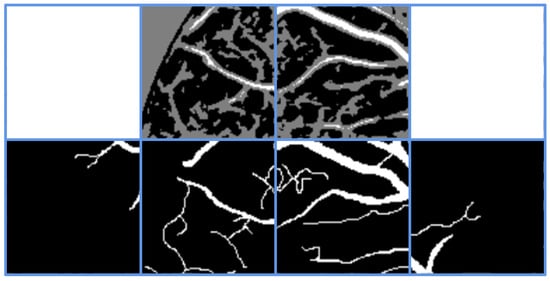

Additionally, due to the overwhelming majority of background pixels over vessel pixels in images, to balance the training between background and vessels and reduce the dominance of background pixels, we directly exclude images with insufficient vessel pixels in pseudo-labels (images with fewer than 100 predicted vessel pixels) from participating in pixel filtering and subsequent training. As shown in Figure 6, the first row displays pseudo-labels, the second row shows corresponding ground-truth labels, and white squares indicate excluded pseudo-label images. It can be observed that images with insufficient vessels are indeed excluded, while images with sufficient vessels are retained as pseudo-labels.

Figure 6. Directly eliminate the image containing too few vascular pixels.

Symmetry 17 01462 g006